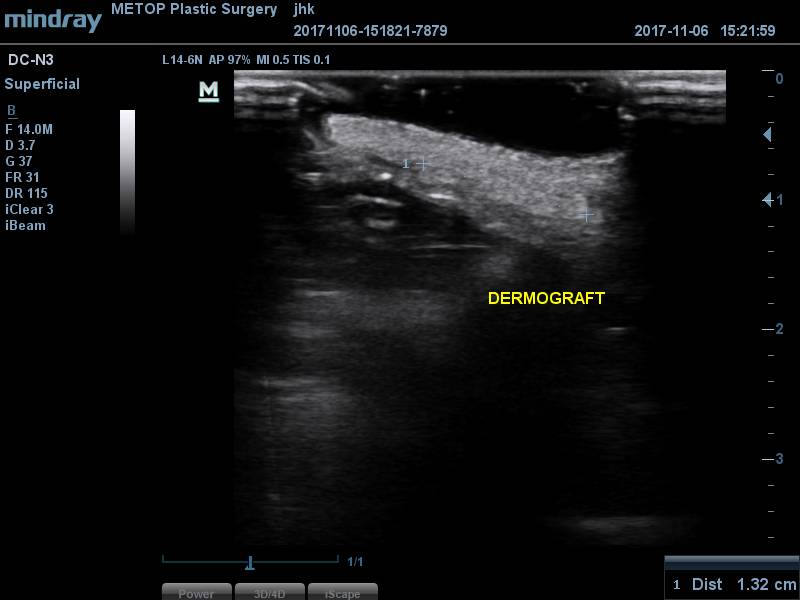

[얼굴이물질제거] 코필러이물질제거

코필러이물질제거